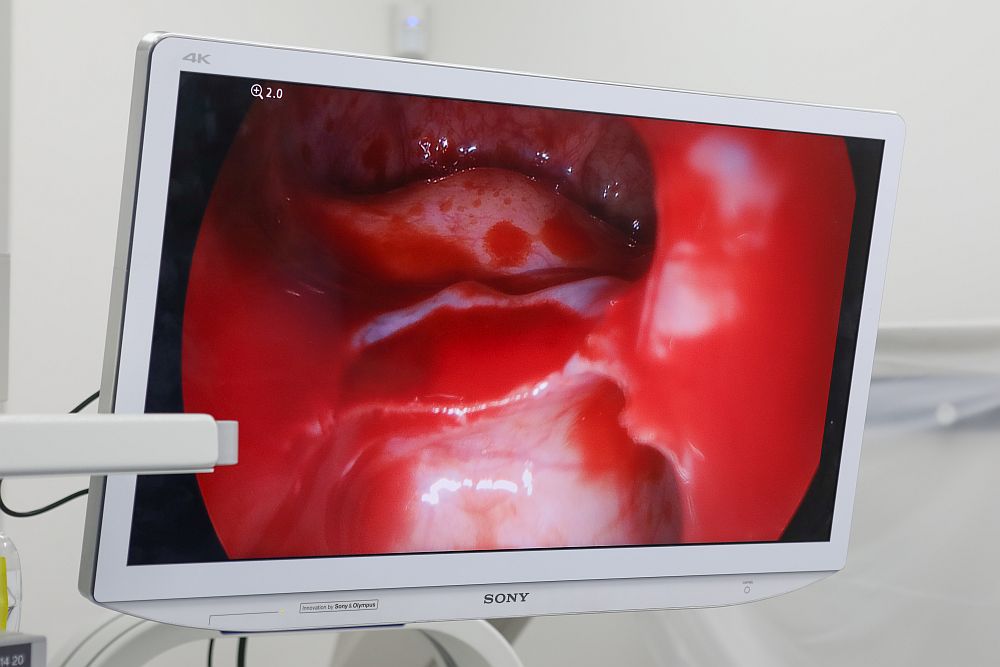

Innowacyjny zabieg udrożnienia zatok w Medical Clinic Podhale